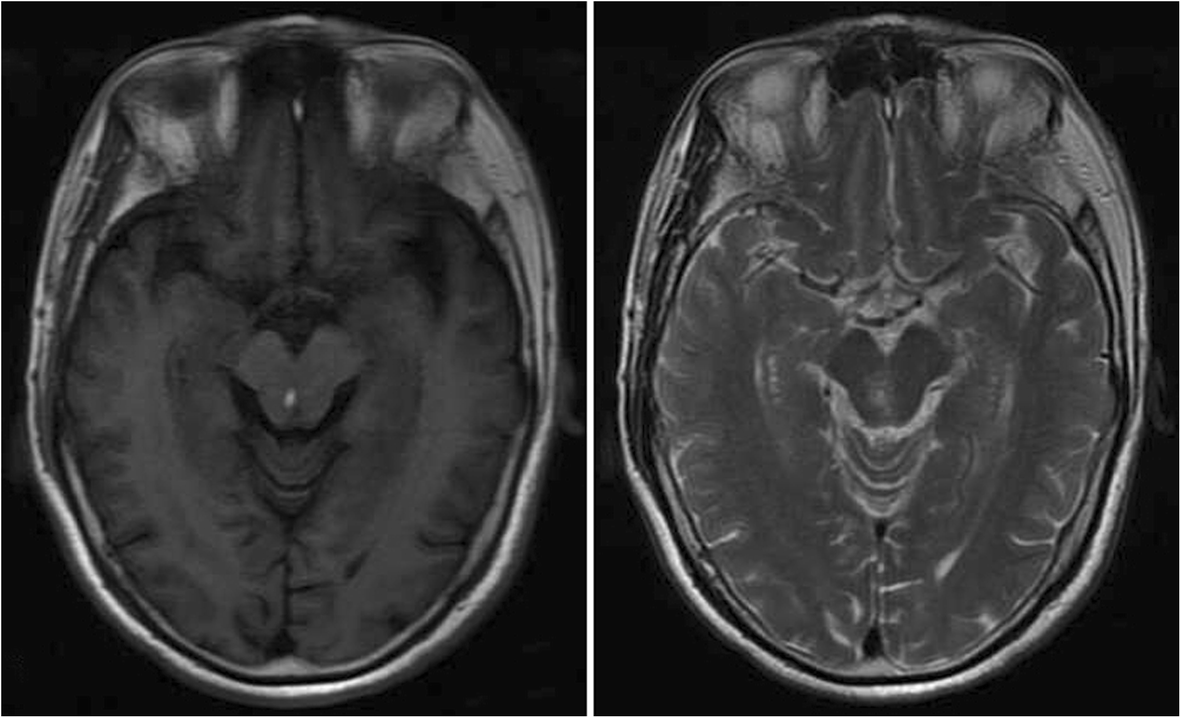

Fig. 3From: A rare long-term undetected pheochromocytoma leading to Takotsubo syndrome in an older male patient: a case reportAn abnormal patch signal is shown in the midbrain on cranial magnetic resonance imaging, high signal intensity on the T2-weighted imaging, and higher signal on the T1-weighted imagingBack to article page